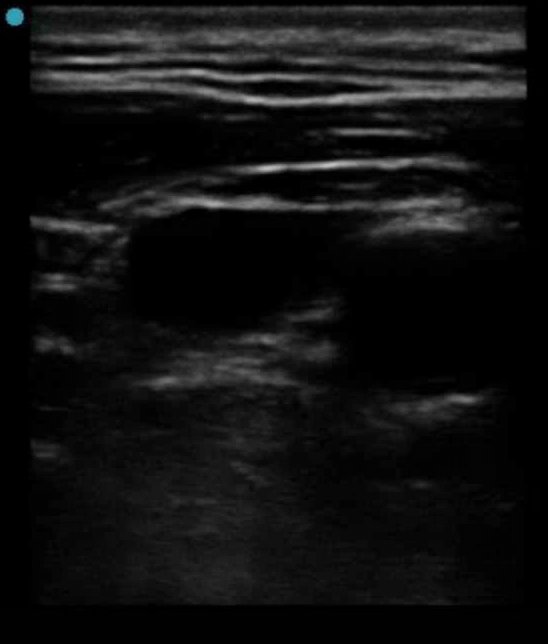

Seemed like a reasonable-sized pocket, and had signs of complexity (hyperechoic content, did not appear to be "free flowing). Given this and concern for empyema, plan was for thoracentesis, and if purulence or high risk features on fluid analysis, convert to pigtail.

Thoracentesis was attempted using long 18 g angiocath, but no fluid was able to be aspirated. Live ultrasound guidance was used, which verified needle in the intended location.

(Image is undergained, turn up screen brightness to see)

still image of needle in intended location

-Malignant pleural thickening can mimic pleural effusion on ultrasound